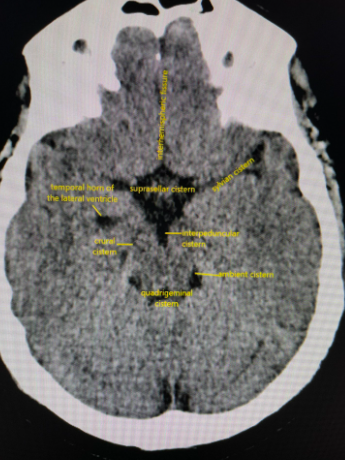

In CT head interpretation, what does ‘Can’ refer to, and what are the 4 main findings?

Can: Cisterns

1. Ambient cistern effacement/blood/asymmetry

2. Suprasellar cistern effacement/blood/asymmetry

3. Quadrigeminal cistern effacement/blood/asymmetry

4. Sylvian cistern effacement/blood/asymmetry

What is a cistern, and how many are there on a CT head?

Cisterns: Outpouchings in subarachnoid space, due to uneven distance between pia mater and arachnoid mater

1. Ambient cistern: Ring surrounding midbrain

2. Suprasellar cistern: Pentagon-shaped

3. Quadrigeminal cistern: Smile-shaped

4. Sylvian cistern: Upper outer corners